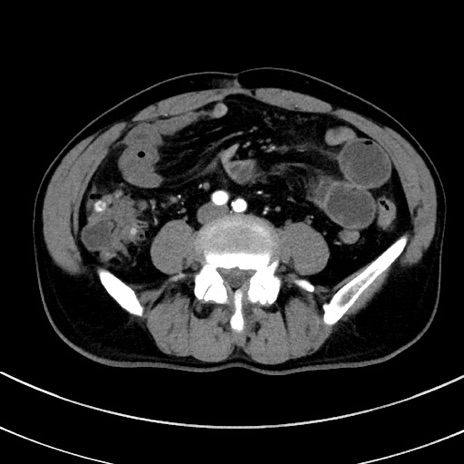

症例8(横断像)

【症例】 60歳代男性

【主訴】 黒色吐物

【現病歴】 4日前から嘔気自覚、2日前の朝食後にも嘔気あり、自分で手で嘔吐反射起こし嘔吐したところ血が混ざっていたため受診。

【既往歴】 5年前汎発性腹膜炎を伴う急性虫垂炎で手術、高血圧、前立腺肥大症、高脂血症

【身体所見】 腹部正中に手術癩痕あり 腹部平坦・軟圧痛なし膨満感あり

【データ】WBC 8400、CRP 4.54